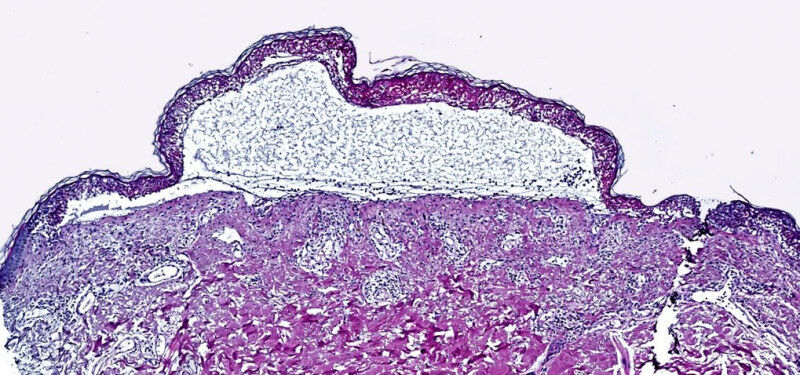

Spatial proteomics provides therapeutic approach for patients with toxic epidermal necrolysis

The researchers used spatial proteomics to analyze skin samples from patients with toxic epidermal necrolysis. This cutting-edge approach, known as Deep Visual Proteomics, merges powerful microscopy with AI-driven analysis, laser-guided microdissection and ultimately ultra-high sensitivity mass spectrometry. They zoomed in on individual cells and studied them like never before, creating a map of the thousands of proteins driving this deadly reaction.

Toxic epidermal necrolysis is a rare but extremely severe adverse reaction to common medications, such as allopurinol (which is used to treat gout) or certain antibiotics. It causes widespread blistering and detachment of the skin. With a mortality rate of up to 30 percent, it rapidly transforms from a seemingly harmless rash into a life-threatening condition. Until now, no effective therapy existed, with treatment primarily limited to supportive care.